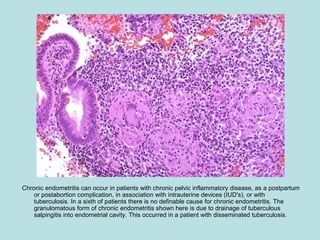

Chronic endometritis can occur in patients with chronic pelvic inflammatory disease, as a postpartum

or postabortion complication, in association with intrauterine devices (IUD's), or with

tuberculosis. In a sixth of patients there is no definable cause for chronic endometritis. The

granulomatous form of chronic endometritis shown here is due to drainage of tuberculous

salpingitis into endometrial cavity. This occurred in a patient with disseminated tuberculosis.